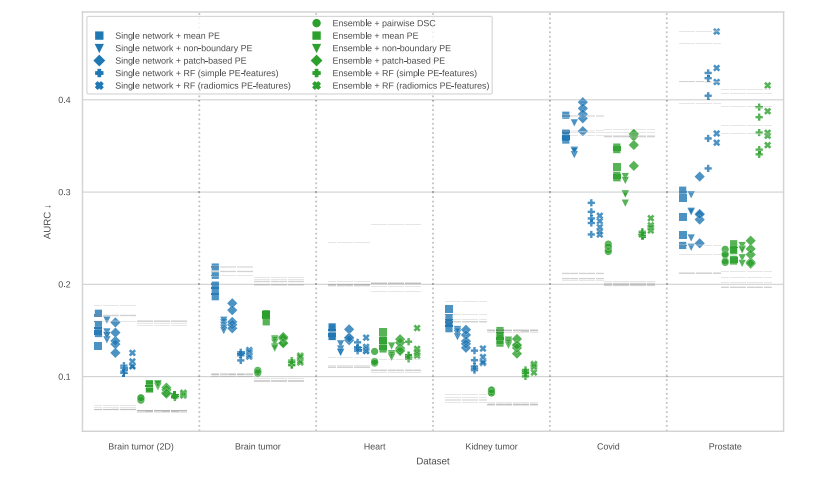

Fig. 3. Comparison of aggregation methods from Section 4.4.2 in terms of AURC scores for all datasets (lower is better). The experiments are named as ‘‘prediction model +confidence method’’ and each of them was repeated using 5 folds. Colored markers denote AURC values achieved by the methods, while gray marks above/below them are AURCvalues for random/optimal confidence rankings (which differ between the models trained on different folds; see Section 4.1). Pairwise DSC scores consistently best, but does notapply to single network outputs. Aggregation methods based on regression forests (RF) also show performance gains compared to the mean PE baseline, but fail catastrophicallyon the prostate dataset, possibly due to the small training set size. PE: predictive entropy. RF: regression forest.

图3. 比较第4.4.2节中的聚合方法,按所有数据集的AURC得分进行比较(得分越低越好)。实验名称为“预测模型 + 置信度方法”,每个实验使用5折交叉验证重复进行。彩色标记表示方法所达到的AURC值,而其上方/下方的灰色标记表示随机/最优置信度排名的AURC值(这些值在不同折次训练的模型之间有所不同;见第4.1节)。成对的DSC得分表现 consistently最好,但不适用于单一网络输出。基于回归森林(RF)的聚合方法相较于均值PE基线也表现出了性能提升,但在前列腺数据集上出现了灾难性失败,可能是由于训练集较小的缘故。PE:预测熵。RF:回归森林。